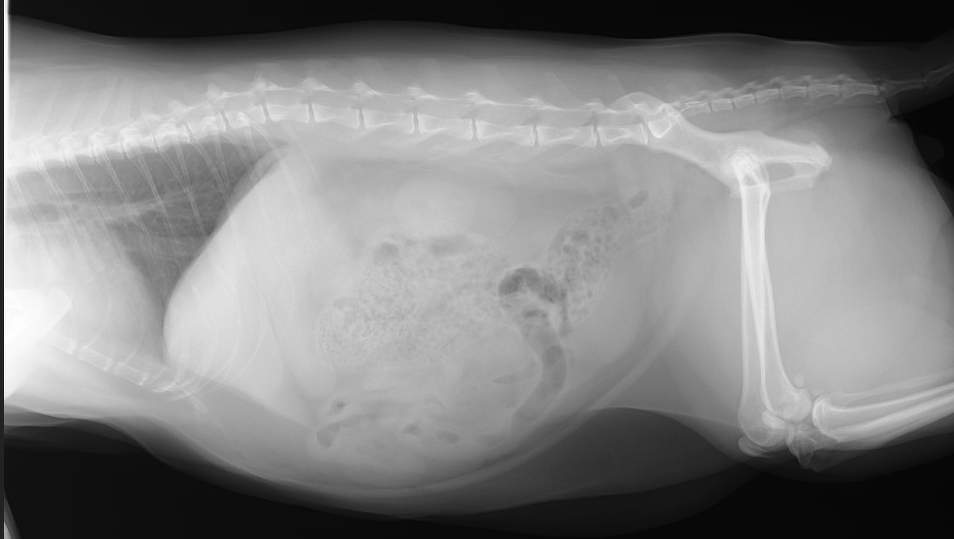

これはオスの肥満した猫のレントゲン写真です。腹囲が膨満し、肝臓が少し大きくなっているので、食欲不振が起こると脂肪肝に発展する可能性が心配されます。